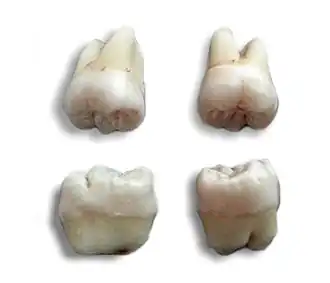

La dent de sagesse est le nom usuel donné chez l'être humain à la troisième molaire, la dernière située à l'arrière de l'arcade dentaire. Son éruption se produit généralement entre 16 et 25 ans, bien qu'elle puisse être inconstante et même ne jamais survenir. Un adulte en possède généralement quatre, mais certaines personnes peuvent en posséder moins, ou même plus.

Les dents de sagesse sont des vestiges des troisièmes molaires des hominidés qui se sont spécialisées pour mieux dilacérer la nourriture coriace (noix, tubercules, viande crue)[8]. Chez l'Homme moderne, la réduction de la taille des mandibules associée à une diminution du prognathisme avec le recul du massif facial en bas et en arrière, est liée à une alimentation plus molle (grâce notamment à la cuisson des aliments) et moins ligneuse, ainsi qu'à la disparition de l'emploi des dents en tant qu'outils[9]. Leur éruption pose assez fréquemment problème du fait du manque d'espace entre la deuxième molaire et la branche montante de la mandibule[10].

- soit car son axe d'éruption n'est pas correct. Les dents de sagesse ont souvent des axes d'éruption fantaisistes, et des formes très variables.